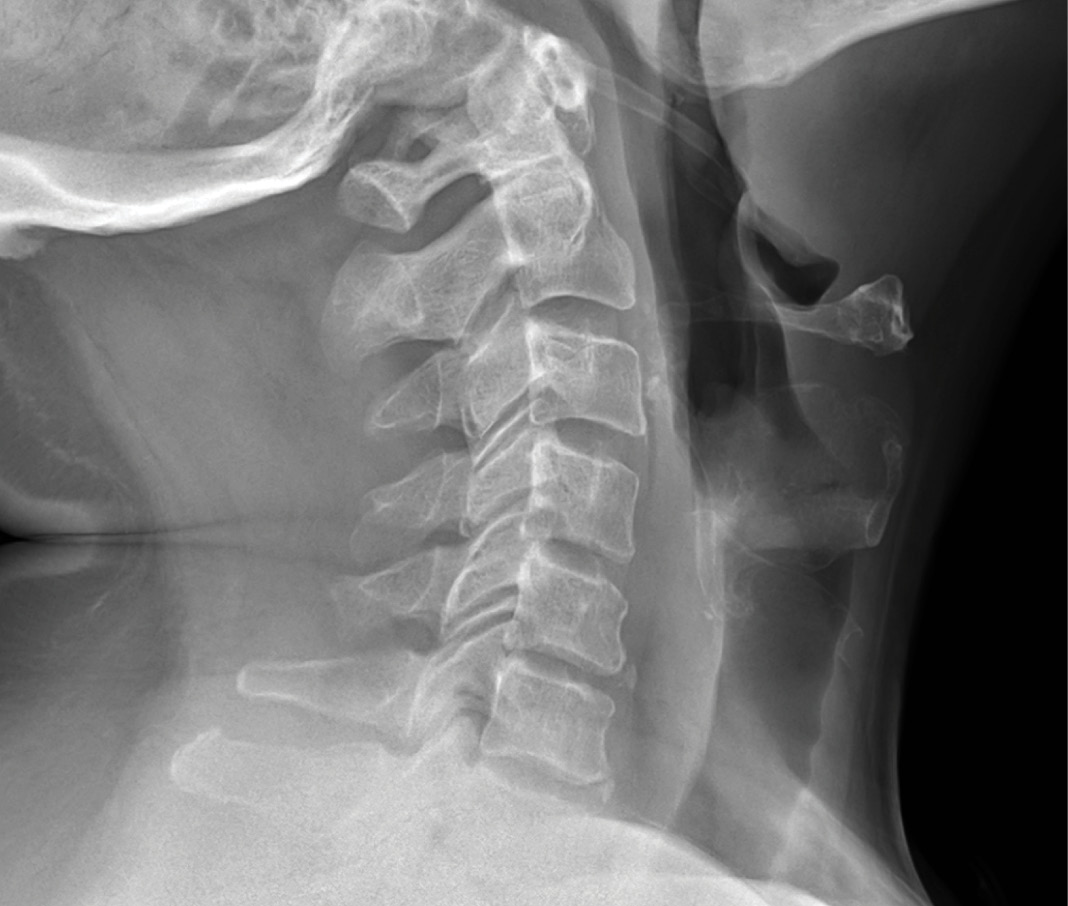

MRIs illustrated mild degenerative disc disease from C4-6 with disc herniations at both C4-5 and C5-6. The axial slice through C4-5 showed a right central disc herniation causing central and mainly right-sided foraminal stenosis. The axial slice through C5-6 showed a central disc herniation also causing central and mainly right-sided foraminal stenosis. The axial slice through C6-7 showed a left-sided disc herniation causing some left-sided foraminal stenosis, however, the patient did not demonstrate any left-sided symptoms.

Upon examination, the patient had good motion on flexion-extension, so fusion was not considered at all. My operative plan was to use prodisc cervical devices and replace both discs at C4-5 and C5-6, giving me the flexibility to use either a domed or flat implant.